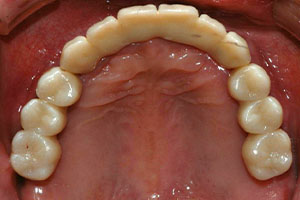

치료증례 전후사진

Before & After